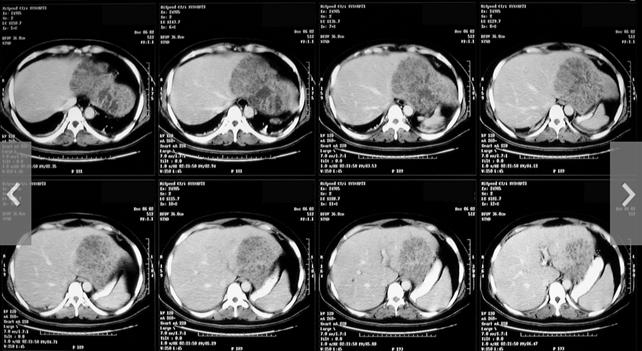

-Siêu âm gan mật cho thấy hình ảnh đặc trưng của ổ áp xe có bờ rõ nhưng áp xe nhỏ quá đôi khi bỏ sót chẩn đoán. Khối áp xe thường ở các vị trí thuộc hạ phân thùy của gan phải, hiếm khi nhìn thấy ở thùy vuông hay hạ phân thùy 1, có lẽ do cấu trúc giải phẩu và tính ưu thế;

-Chụp cắt lớp vi tính hay chụp cộng hưởng từ (CT-scan hay MRI) cho thấy hình ảnh sang thương có bờ rõ nét nhưng hiếm khi chỉ định và công cụ này có giá thành mỗi lần chụp cao. Một số ca nếu can thiệp chụp cắt lớp như ca áp xe làm thủng một mạch máu to gây chảy máunặng, áp xe có thể lan rộng vào vùng lân cận màng phổi, phổi, màng ngoài tim, màng bụng, tụy,…